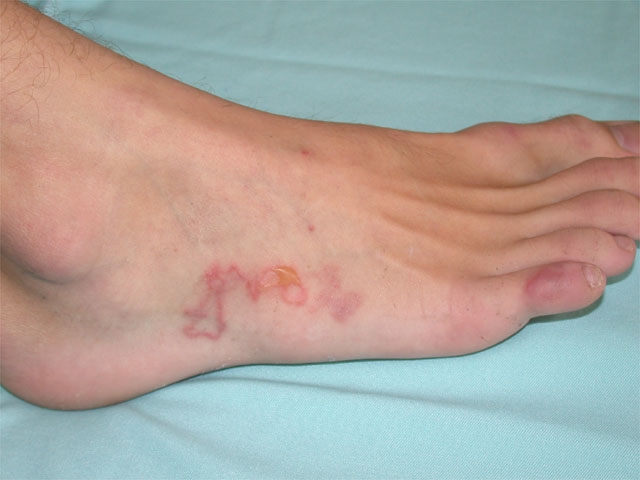

A 34-year-old man comes to the office during summer due to intensely pruritic lesions on his right foot.  The patient has no chronic medical conditions and has never had similar symptoms before.  He smokes a pack of cigarettes daily and drinks alcohol on social occasions.  The patient works as a landscaper and recently went to a company barbeque lunch.  His vital signs are normal.  Physical examination findings are shown below. A 34-year-old man comes to the office during summer due to intensely pruritic lesions on his right foot.  The patient has no chronic medical conditions and has never had similar symptoms before.  He smokes a pack of cigarettes daily and drinks alcohol on social occasions.  The patient works as a landscaper and recently went to a company barbeque lunch.  His vital signs are normal.  Physical examination findings are shown below.   Which of the following most likely occurred before the patient developed these symptoms? A) Bite from a brown recluse spider B) Consumption of undercooked pork C) Contact with plant sap containing urushiol D) Trauma from decaying vegetation E) Walking barefoot on a sandy beach Which of the following most likely occurred before the patient developed these symptoms?